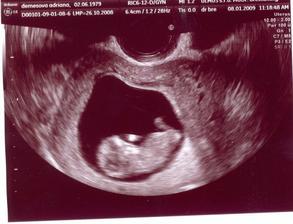

15.01.2009 nás čaká ďalšie sono:D, už teraz sa teškáme....08.01.2009 špinenie, panika...tak šups doktorovi - predpísal nám Utrogestan, MagneB6 a Ascorutin. Máme si dávať denne dva citróny a dve lyžičky medíku. Dostali sme štipľavú injekciu, ale bábätku našťastie veselo bije srdiečko...a máme pre istotu aj fotečky:D

15.1.2009 sono + fotecka. bábätko robí kotrmelce, máva ručičkami a nožičkami (nech sa blázni, kým má miesto:D). všetko vyzerá byť ok. akurát na ľavom vaječníku mi dr.objavil cystu. hádam bude všetko ok.....